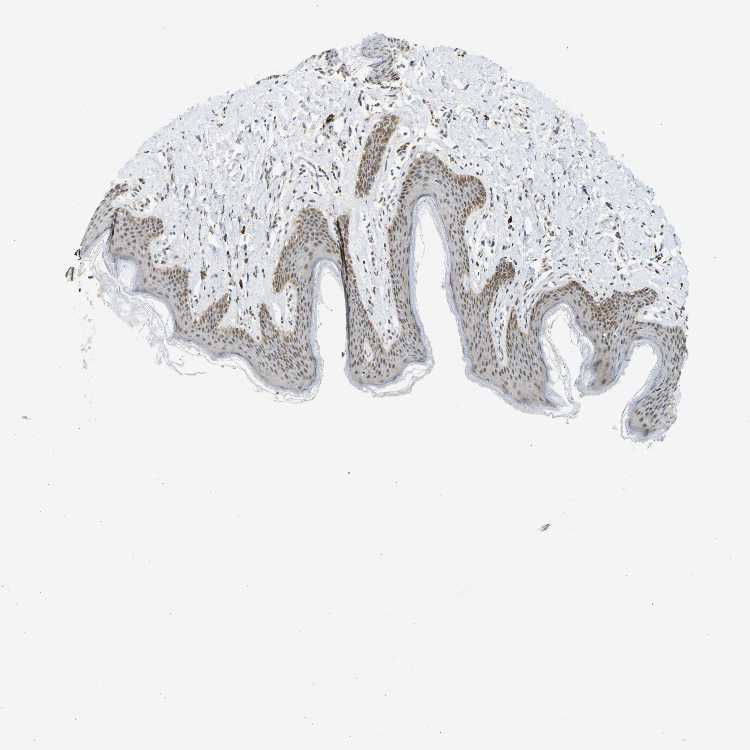

SKIN 1 - Antibody stainingi

Antibody staining in the annotated cell types in the current human tissue is reported as not detected, low, medium, or high, based on conventional immunohistochemistry profiling in selected tissues. This score is based on the combination of the staining intensity and fraction of stained cells.

Each image is clickable and will lead to virtual microscopy that enables deeper exploration of all samples and also displays staining intensity scores, fraction scores and subcellular localization as well as patient and tissue information for each sample.

Antibody HPA019824Antibody CAB015201

Langerhans LowNot detected

Fibroblasts Not detectedLow

Keratinocytes LowLow

Melanocytes LowLow